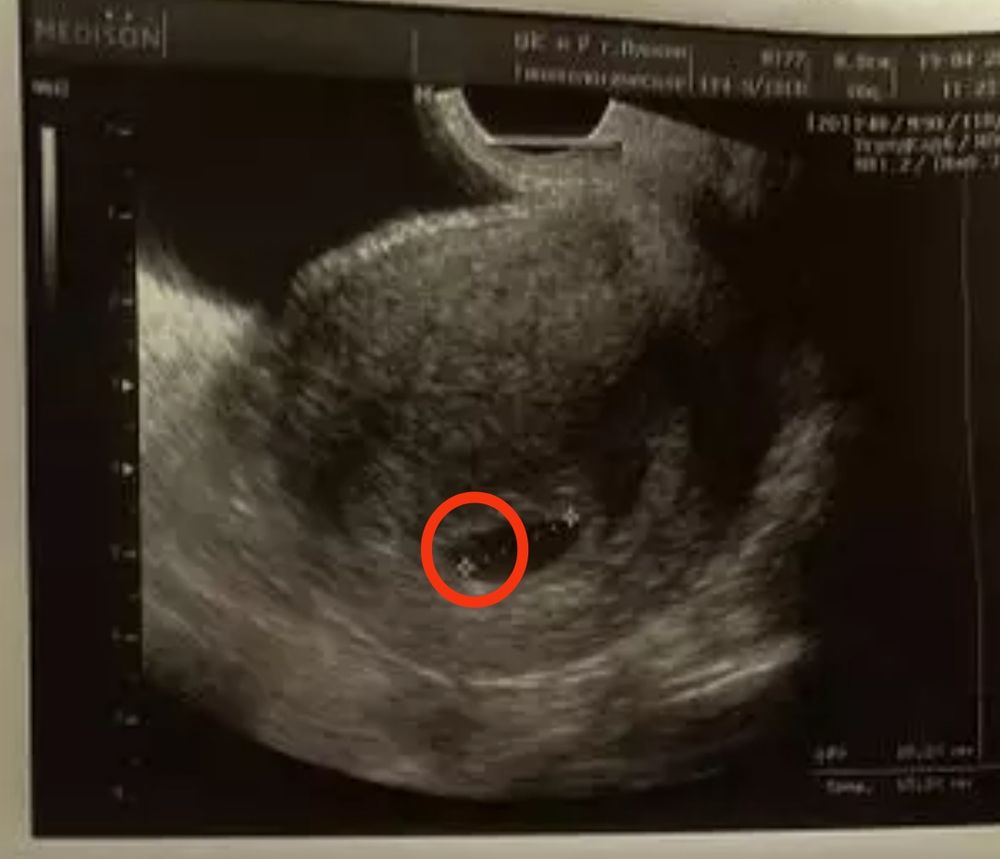

Первое узи, плодное яйцо

Арина Калашникова, я не эксперт,но по фото,похоже,что вот жм Изображение

19.04.2022

Марина, нет, это отметка(( (измерение пя от точки до точки)

Марина, а, или вроде за этой отметкой что-то виднеется? Я сейчас присмотрелась

Арина Калашникова, там кружочек такой,возле отметки

Марина, да, вроде и правда похоже !